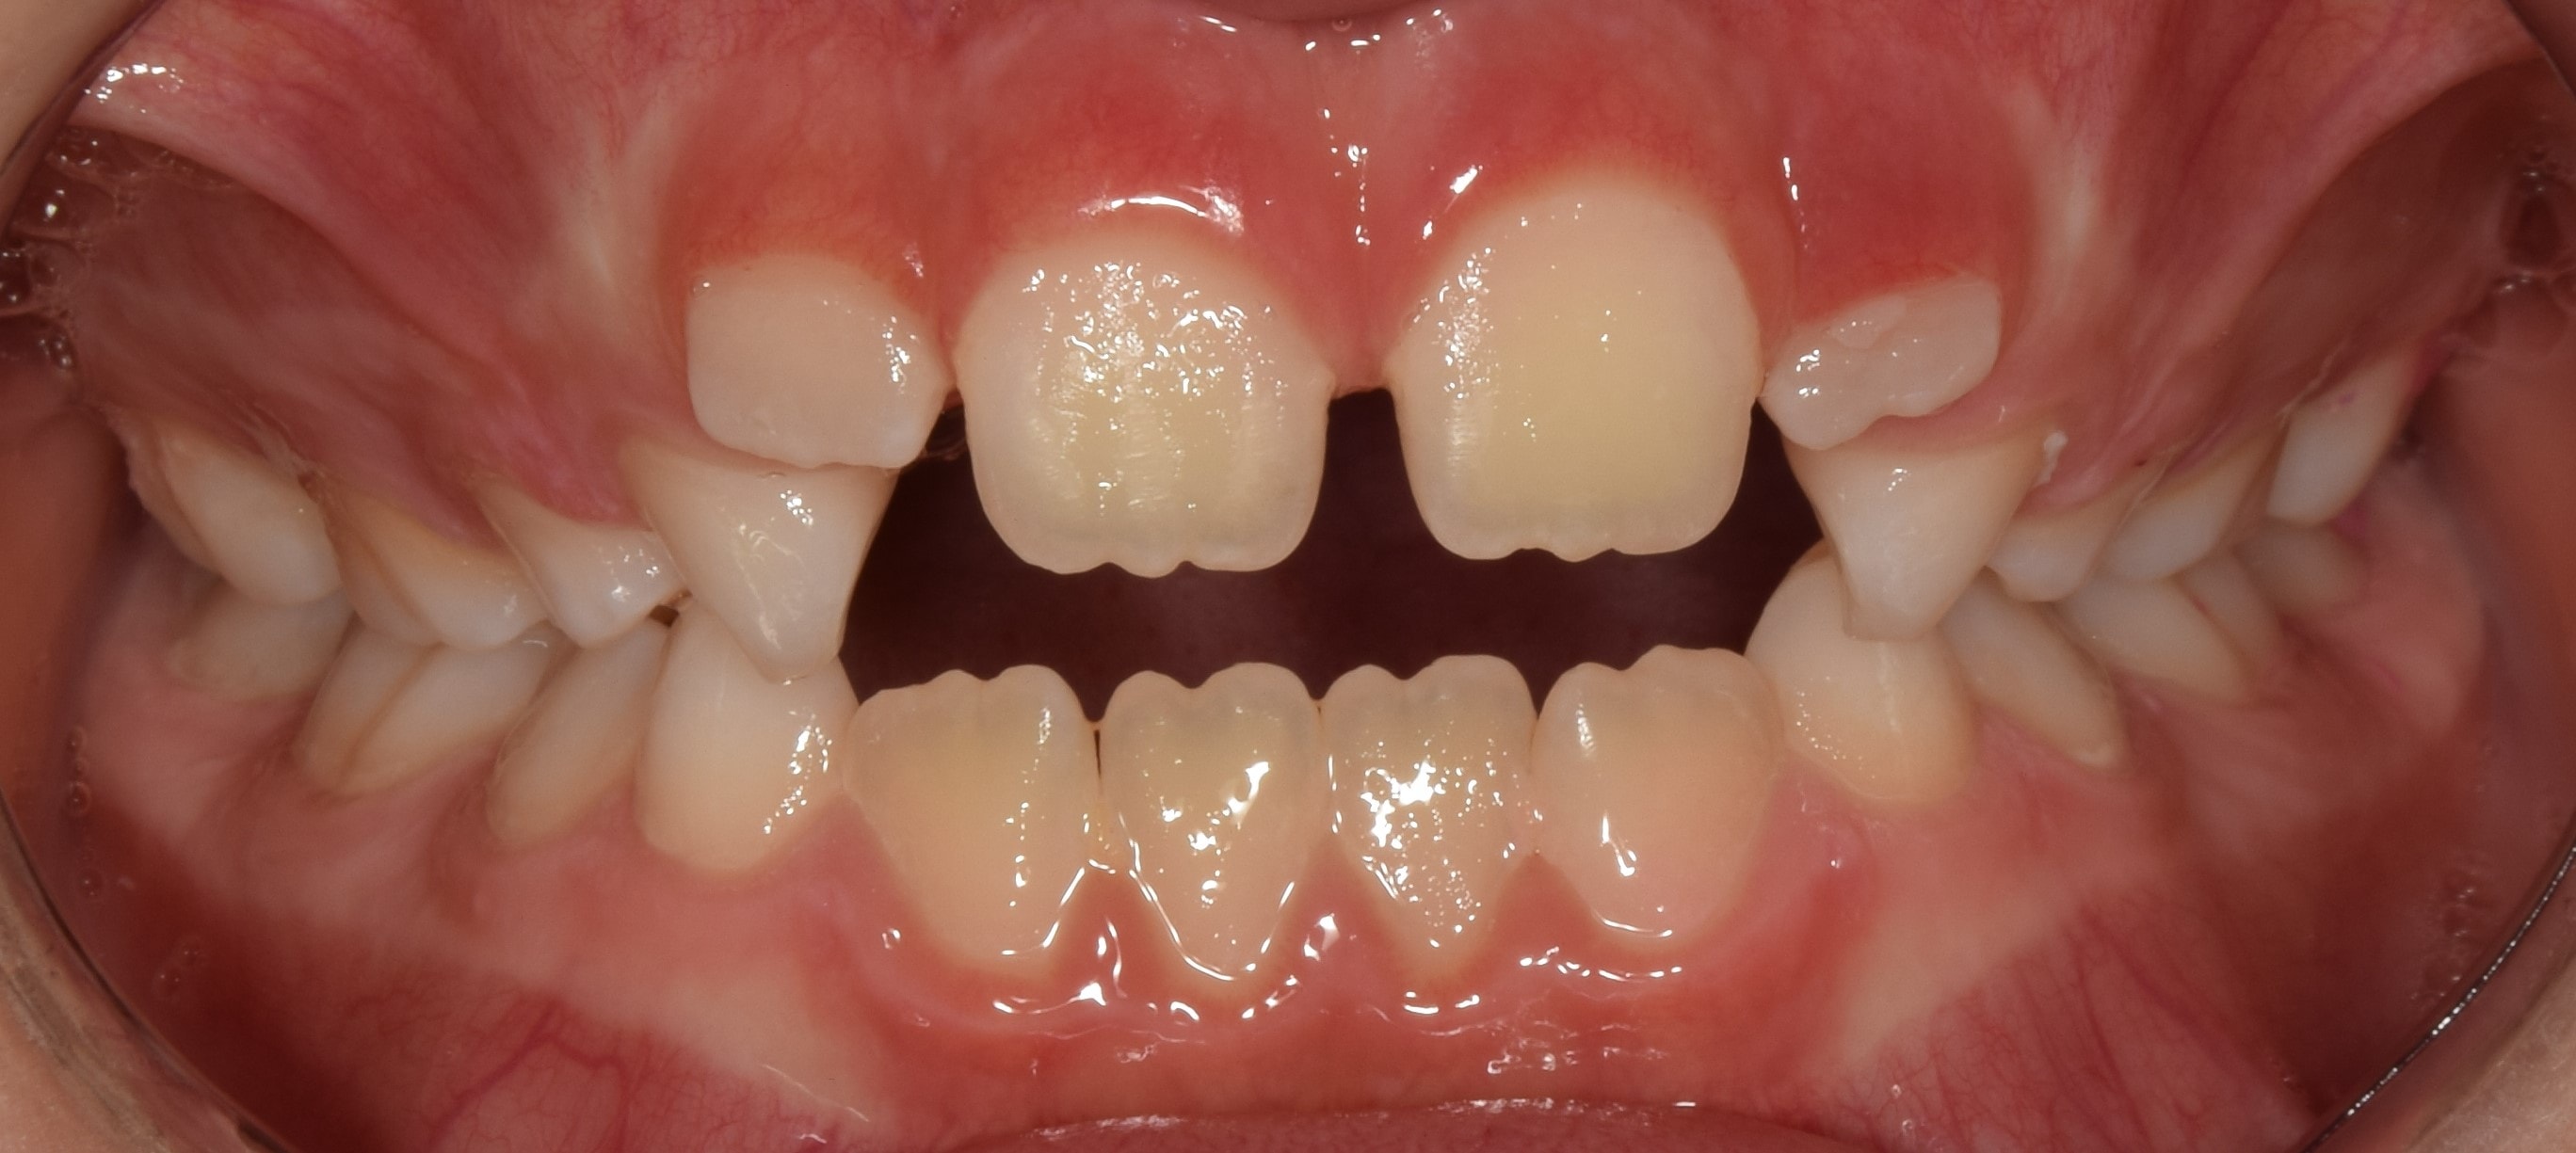

Korai vegyesfogazat

7-8 éves kor körül a gyermekek többségének korai vegyesfogazata van. Ez azt jelenti, hogy az első maradó nagyőrlők előtörtek, a tej metszőfogakat pedig felváltották a maradó metszőfogak.

Fiatalkorban a felső állcsont tágítására alkalmas rögzített fogszabályozó készülék. Működése a felső állcsont közepén található csontvarrat (sutura palatina mediana) megnyitásán alapszik. Ilyenkor a két állcsontfelet távolítjuk egymástól. A hyrax maradófogazatban a felső első kisőrlőkön és első nagyőrlőkön rögzül, vegyesfogazatban pedig az első maradó nagyőrlőn és a tejőrlőkön (esetleg tej szemfogon). A vegyesfogazati hyrax készülhet fémből, vagy akrilátból (ez a splint hyrax). A hyrax közepén, a szájpad mélyére süllyesztve található egy csavar, amelyet a pácienseknek, szülőknek otthon kell tekerni. Fiatalkorban (7-9 év) ez 3 naponta 1 tekerést jelent, míg később (9-12 év) naponta 2 tekerést. A készülék működése során a felső állcsont tágul, a mosoly szélesedik, a torlódások spontán oldódnak, és a felső metszőfogak között rés keletkezik (ez idővel magától zárul). A felső állcsont tágulásával az alsó állcsont gyakran spontán előrehelyeződik (megoldva ezzel pl. egy disztálharapást). Átjárhatóbbá válnak a légutak, javul a szervezet és az agy oxigenizációja, ezzel a gyerkőcök alvása, kipihentsége, koncentrációja. Általam sokat használt és kedvelt készülék a hyrax. Fontos megjegyeznem, hogy a fent leírt, ijesztően hangzó mozgatások a pácienseim beszámolói alapján semmilyen fájdalommal nem járnak, és bár drasztikusnak tűnhet a folyamat, a gyerekek által egyik legjobban tolerált készülék. Kezelés hossza: 7-12 hónap. Kontrollok gyakorisága: az első 2-3 hétben hetente, később 4-8 hetente. A kezelés befejeztével vagy Goshgarian kerül fel az eredmény megtartására, vagy teljes rögzített fogszabályzó ragasztásával folytatódik a terápia.